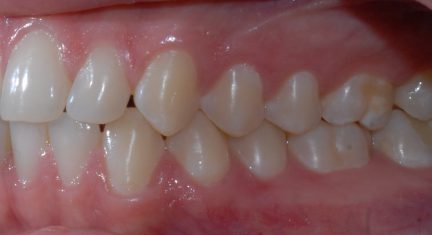

Classe I, arcades étroites, chevauchement, espacement, diastème

État initial